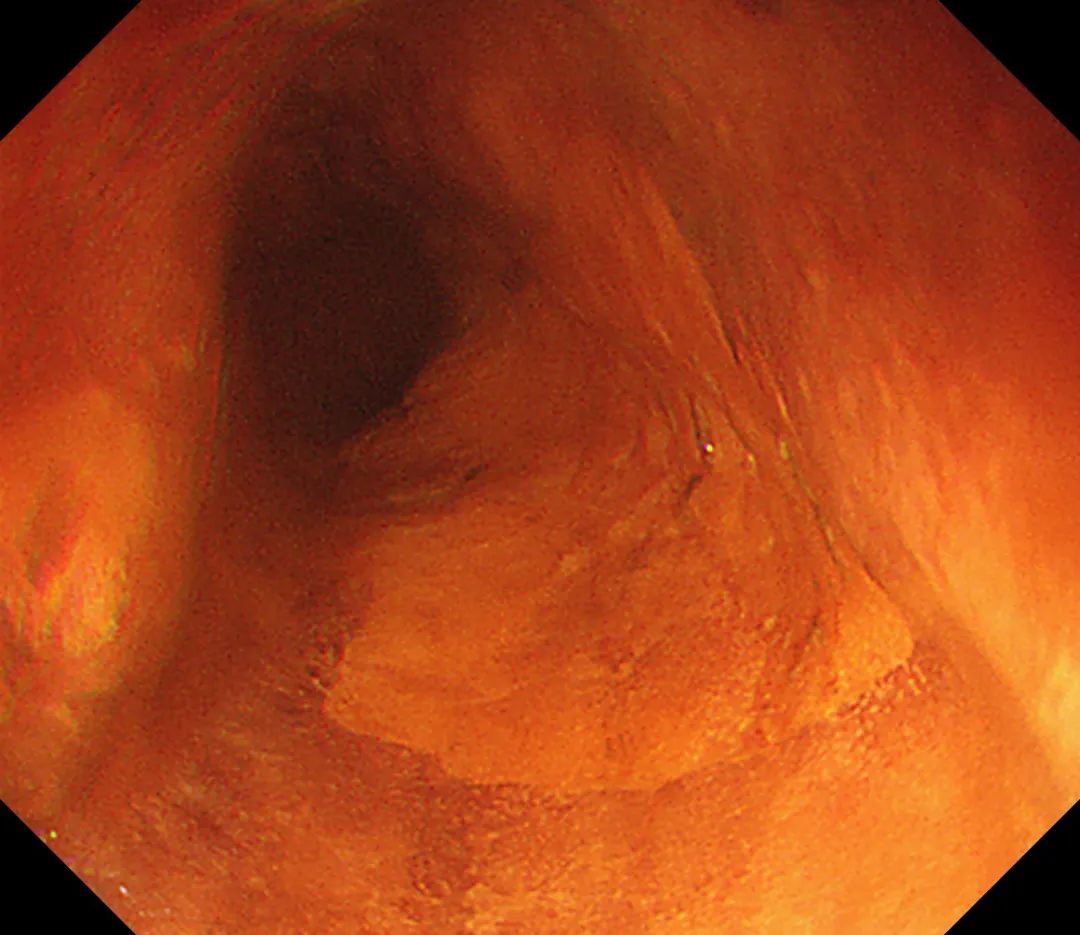

今年65岁的李老是一名退休职工,平日里下下棋、溜溜弯、带带孩子,享受着惬意的退休生活。不过由于家族有消化道肿瘤的病史,这些年他越来越重视自己的健康问题,定期都会到济源二院的消化内镜室做检查。而就在最近的一次检查中,他的食管部位被发现有异常,经过初步筛查,考虑为食管中上段黏膜高级别上皮内瘤变。

“这其实就是消化道早癌的一种,”二院消化内镜室主任田晓丽解释说,消化道早癌指粘膜下层轻度浸润(SM1:<500μm)或者仅仅局限在粘膜层的消化道肿瘤。“通俗讲,就是早期癌症,仅限于粘膜及粘膜下层的肿瘤性病变或者癌前病变。”消化道早癌主要包括早期食管癌、早期胃癌以及早期结肠癌。

“局限在黏膜层及黏膜下层浅层的消化道早癌,可以通过超级微创的办法,在内镜下进行黏膜剥离去除。经胃肠镜检查发现后的早期病变,再经过详细的内镜下放大、染色、超声等检查后初步判断其范围和深度,对于适合内镜下诊治的病变可选用经内镜黏膜下剥离术(ESD)或内镜下粘膜切除术(EMR)处理。”周主任对消化道早癌的治疗方法进行了介绍,“它创伤小,能够避免更加复杂的外科手术。”

在周主任娴熟地操作下,细细的胃镜渐渐深入到李老的病灶处......四十分钟过后,手术顺利完成,一觉醒来,李老已经躺在了宽敞的病房里。